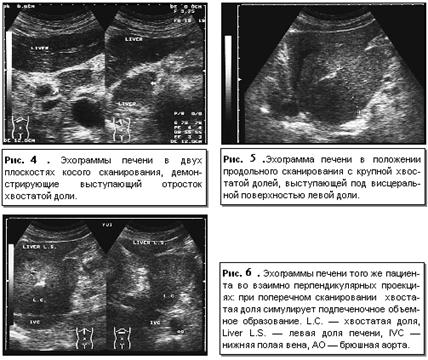

долями. Хвостатая доля имеет в той или иной степени ярко выраженный хвостатый

отросток, располагающийся на эхограммах кзади от ворот печени, кпереди от

нижней полой вены и в латеральном направлении от основной массы хвостатой доли.

Причем при достаточно больших размерах хвостатый отросток может значительно

выступать со стороны висцеральной поверхности печени (рис. 4, 5 ,6).